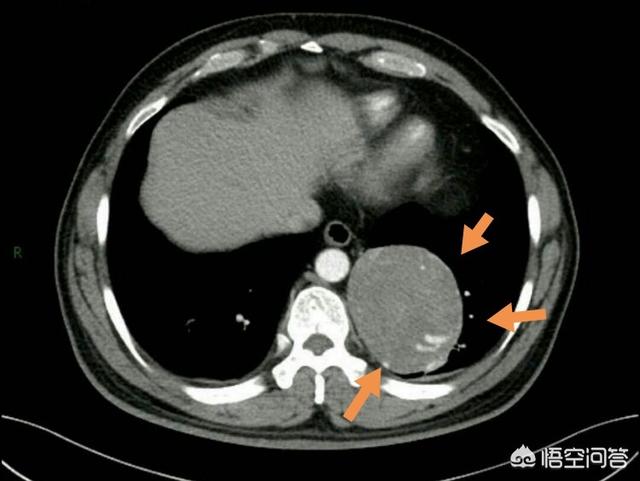

この患者は喀血により肺に大きな腫瘍が見つかり、その病態は硬化性肺細胞腫、以前は硬化性肺血管腫と呼ばれていたもので、良性であるが悪性の傾向があると調査され、後に手術で摘出され、リスクも軽減された。

この患者のように、良性の平滑筋腫瘍が気管に発生し、気管狭窄や呼吸困難を引き起こしている場合、腫瘍を除去する手術が必要となる。

逆に、良性腫瘍の中には悪性の可能性があり、将来のある時点で癌化する可能性があるものや、腫瘍が比較的大きく、臓器機能に支障をきたすため外科的切除が必要なものもある。

例えば、比較的大きな骨軟骨腫、硬化性肺細胞腫、骨の巨細胞腫、消化管の閉塞を引き起こす良性腫瘍などである。